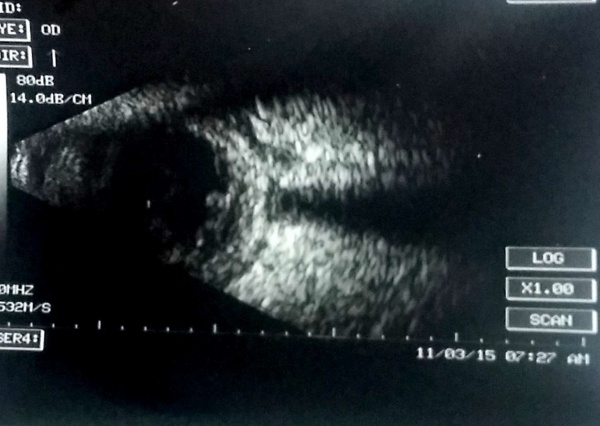

A case of choroidal hemangioma[6] with exudative RD. Note the limited after-movements.